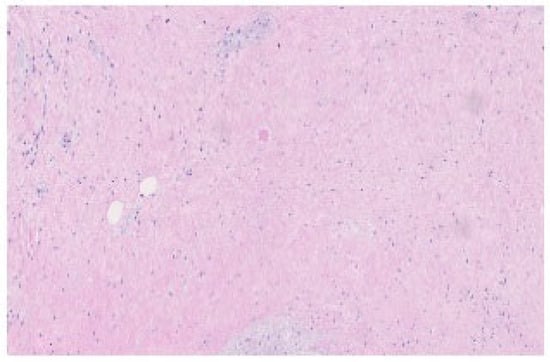

Diffusion Basis Restricted Fraction as a Putative Magnetic Resonance Imaging Marker of Neuroinflammation: Histological Evidence, Diagnostic Accuracy, and Translational Potential -